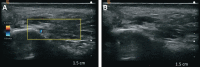

The global market for hyaluronic acid (HA)-based dermal fillers has experienced substantial growth, providing patients with an effective nonsurgical cosmetic option. According to the global market report, the HA dermal fillers market size is expected to grow to $8.5 billion in 2027 at an annual growth rate (CAGR) of 8.9%. However, despite their popularity, HA injections are not free of complications. Vascular occlusion, particularly involving the central retinal artery, represents a significant risk. This case report presents a 60-year-old woman who presented with binocular vertical diplopia after HA filler injection in the right tear trough area. Upon evaluation, the patient exhibited right hypertropia, suggesting right inferior rectus paresis due to vascular injury of the infraorbital artery. Prompt management with hyaluronidase and oral steroids resulted in the resolution of double vision. This case highlights the importance of recognizing potential complications during HA filler injections and emphasizes the need for early intervention to minimize adverse effects.